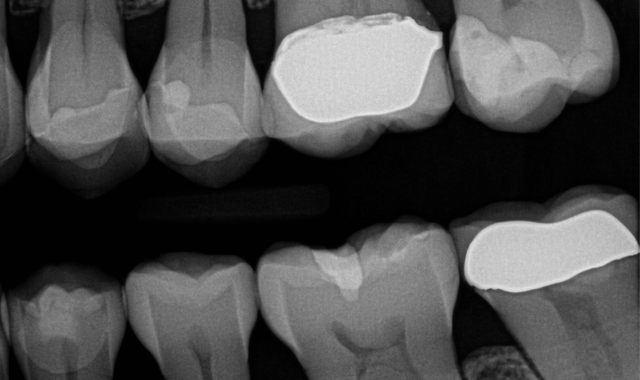

Fig. 1

Fig. 2

A 50-year-old female patient presented for replacement of a fracture and decay in an existing composite restoration (Figs. 1-2). While crowns or onlays would be the typical treatment of choice in our office, the patient will need to put off receiving indirect restorations for a couple years. It was decided that due to the depth of the existing restorations and the recurrent caries present, it would be wisest to perform caries control for the teeth.